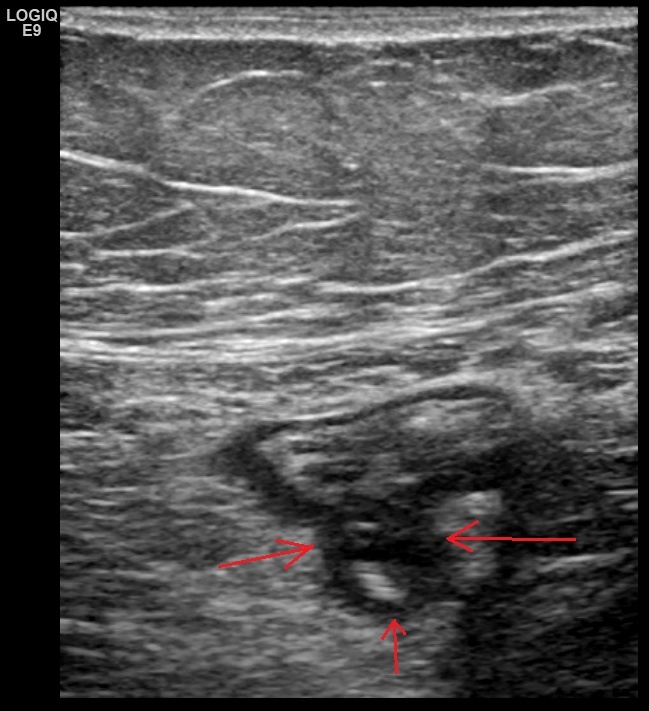

Рис. 15. Это изображение является пояснением к последующему видео. Выполнена дозированная компрессия датчиком в проекции дивертикула (дивертикул указан красными стрелками), и прослеживается смещение пузырьков воздуха через узкую шейку дивертикула в просвет кишки (тонкие зеленые стрелки).